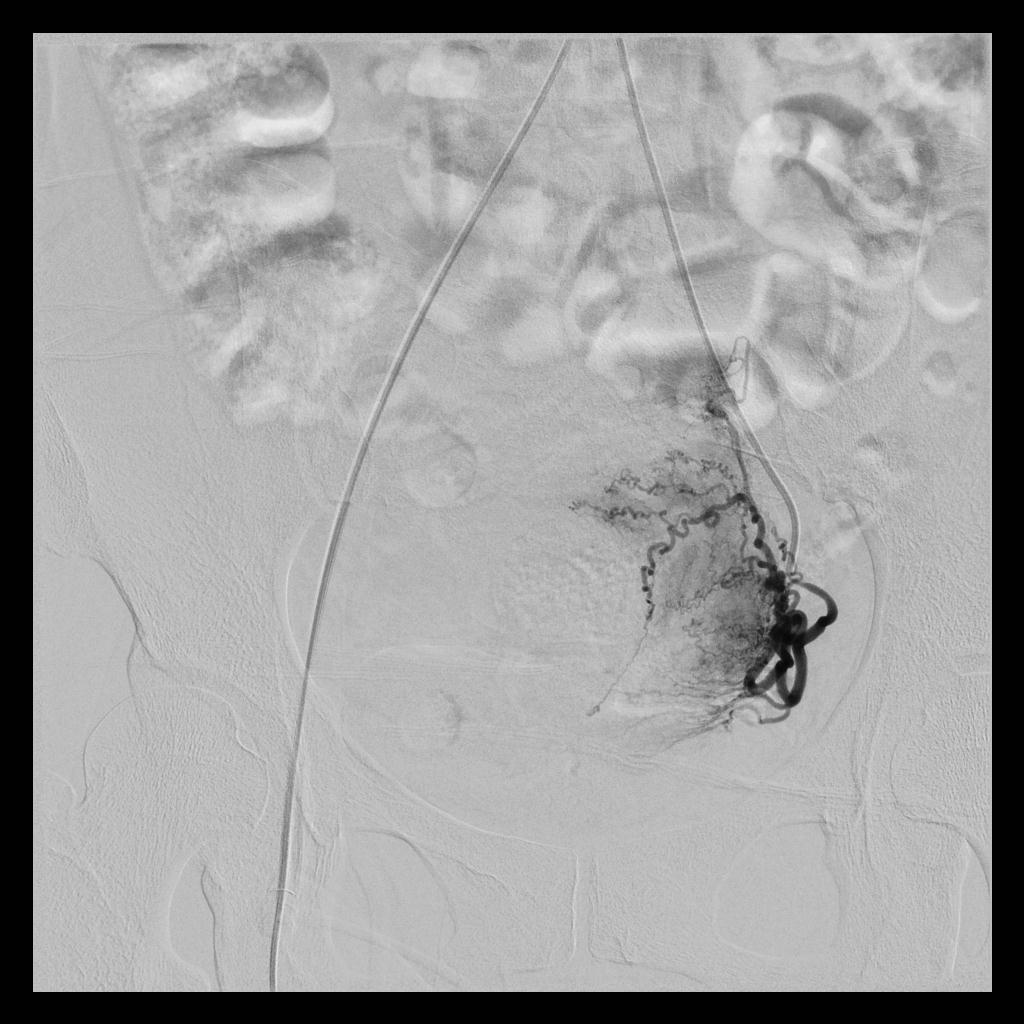

术后,经子宫动脉造影显示:之前增粗、迂曲、供血丰富的子宫动脉,经栓塞术后,血流基本停滞;之前增大的子宫和子宫肌瘤,经栓塞术后,其造影染色也已消失。

(右侧子宫动脉造影:术前、术后)